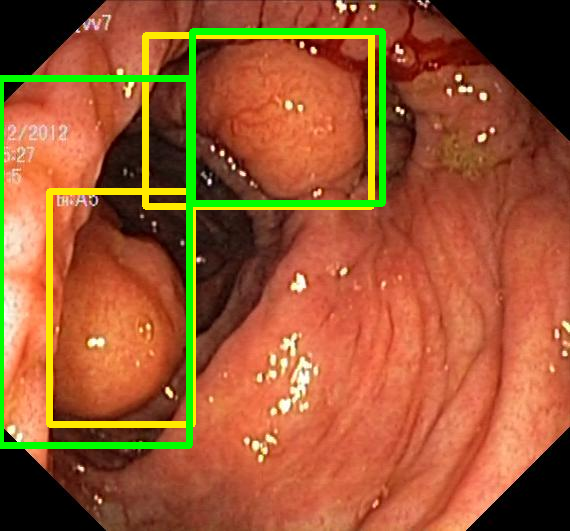

We evaluate the resulting object detection models using the test data, which is pre-processed in the same manner as the validation data, with AP@[.5:.95] (AP for conciseness), AP@.5 (AP50), and AP@.75 (AP75) computed for predicted bounded boxes with a confidence score \geq0.05. For all metrics, a higher value indicates better performance. The results are presented in Table VI, and some examples for predicted bounding boxes with a confidence score \geq0.5 are shown in Fig. 1.

Figure 1: Targets (yellow bounding boxes) and predictions (green bounding boxes) for two randomly selected instances of the Kvasir-SEG test set. For conciseness, we denote ResNet50s with RN, ViT-Bs with VT, Hyperkvasir-unlabelled with HK, ImageNet-1k with IN, MoCo v3 with MC, Barlow Twins with BT, MAE with MA, supervised pretraining with SL, and no pretraining with NA-NA.